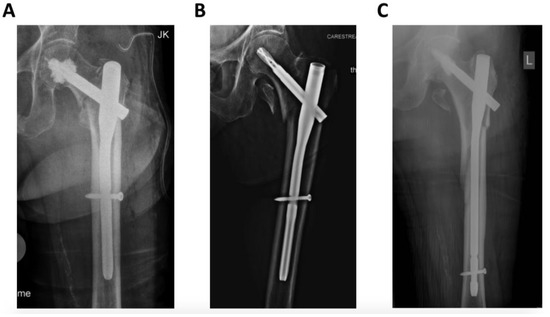

In all cases, surgery was performed under general anesthesia by trauma specialists (seven senior trauma surgeons), according to the AO principles of fracture management. An extension table was used for fracture reduction with open or closed reduction depending on the fracture pattern. Cephalomedullary fixation was achieved with the Proximal Femoral Nail Antirotation (PFNA, DePuy/Synthes, Umkirch, Germany) with additional bone cement augmentation of the helical blade in case of poor bone quality, according to the surgeons’ intraoperative findings (Figure 1).

Figure 1. Radiographic images of different trochanteric fracture patterns according to the revised AO/OTA Classification. (A) = 31A1; (B) = 31A2; (C) = 31A3.